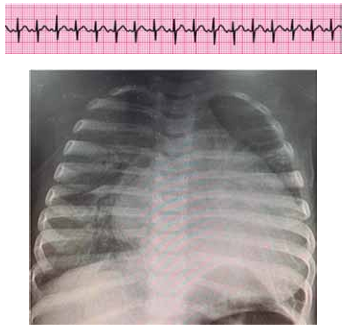

Lactente de 6 meses com tosse, coriza e desconforto respiratório progressivo há 2 dias (chega a ficar “roxinho” nos lábios quando mama, segundo a mãe). Nega internações ou problemas de saúde prévios. Foi trazido ao pronto-socorro devido a piora do desconforto, palidez cutânea e inapetência, com importante comprometimento do estado geral. Ao exame físico, está em mau estado geral, descorado +++/4+, extremidades frias, tempo de enchimento capilar de 5 segundos, pulsos finos, FC = 200 bpm, PA = 62 x 33 (43) mmHg, SatO2 = 87% em ar ambiente, FR = 68 ipm, ausculta pulmonar com estertores crepitantes em bases e ausculta cardíaca com bulhas rítmicas normofonéticas com sopro sistólico +/6+ em borda esternal esquerda. Obtido ritmo cardíaco e radiografia de tórax a seguir.

(Arquivo pessoal; imagens usadas com autorização)